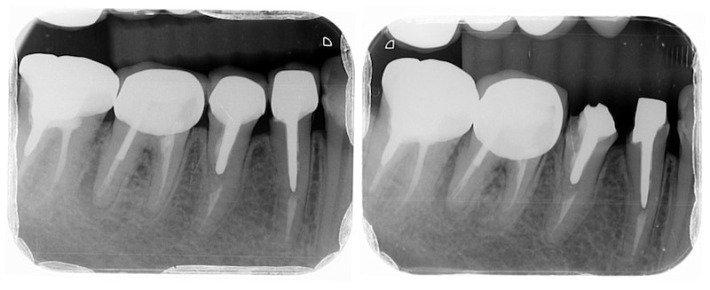

Pictured: A full-mouth examination of the patient before periodontal disease treatment revealed that only the remaining roots of the large molars were decayed.

In addition, patients also have high rates of tooth decay and gum recession that exposes tooth roots, which are all causes of tooth sensitivity and soreness.

Picture: The patient has exposed tooth roots, gum inflammation and tooth decay.

In addition to evaluation and treatment when diagnosing dental caries, I will also use a periodontal probe and X-rays to specifically check whether the patient's periodontal condition poses potential risks. The diagnosis of periodontal disease is full-mouth mild periodontitis. This mild periodontal disease can usually be well controlled with regular six-monthly dental calculus removal (dental scaling) and improved oral hygiene education.